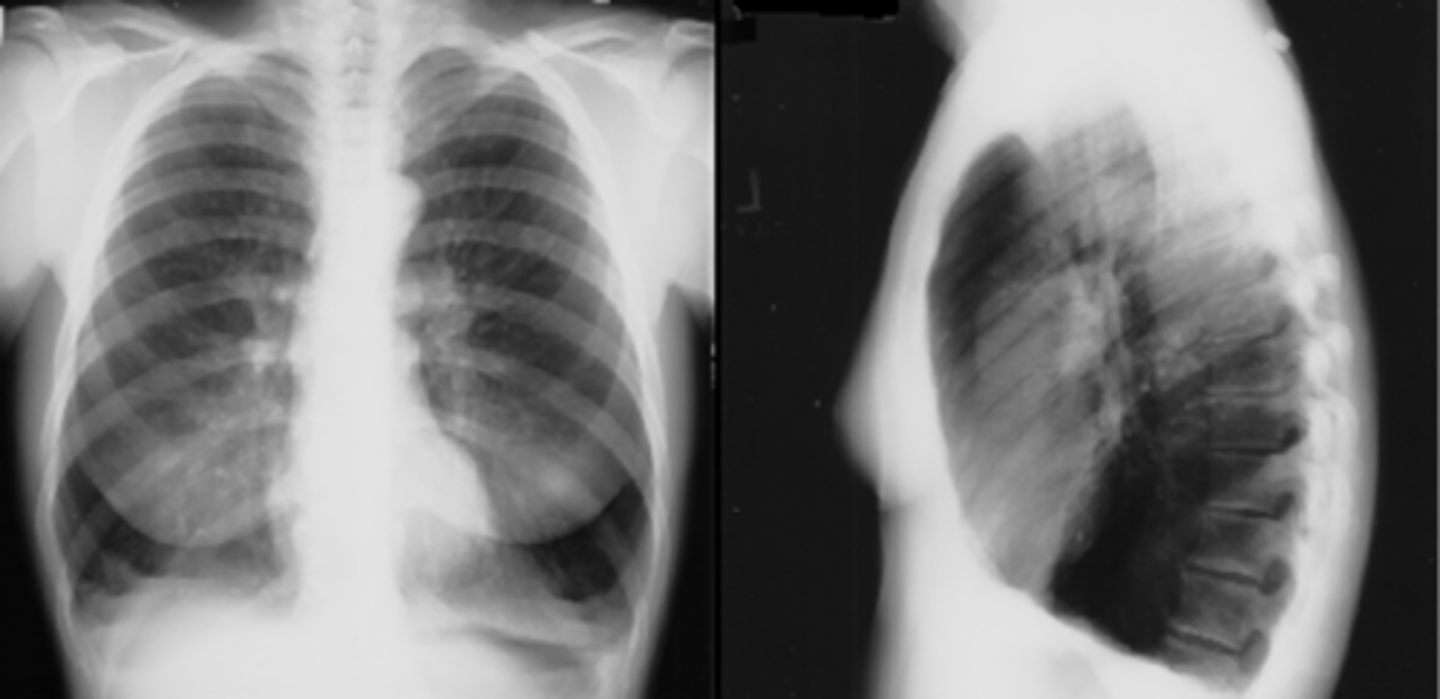

Bronchiectasis

knowt flashcard image

Tram track lines